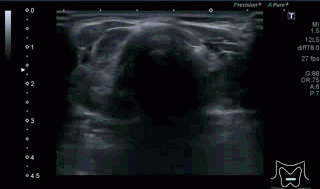

Era un nódulo hiperecogénico en el contexto de la tiroiditis en el estudio de una ecografía tiroidea.

Te enseño las imágenes, típicas de una exploración tiroidea de protocolo con semiología de tiroiditis.

De la imagen 1 a 7 el protocolo habitual, el estudio particular del nódulo con medidas y aplicación del doppler demuestra el aspecto típico del Caballero Blanco.

Resumen de las imágenes que has visto en el caso de hoy:

- Hipoecogenicidad del parénquima

- Heteroecogenicidad

- Múltiples nódulos hipoecoicos muy pequeños

- Doppler Color y Doppler Power aumentado de tamaño en el nódulo

Este es el aspecto ecográfico descrito anteriormente de la patología que habitualmente puede albergar el nódulo del que trata hoy el post y que no es otra que la de la Tiroiditis de Hashimoto.

El Caballero blanco, recibe el nombre debido a su semiología hiperecogénica, homogénea y solitaria circunscrito en la patología referida con anterioridad, puede aparecer en esta patología de forma benigna o degenerar en otro tipo de patología a formas malignas como el linfoma tiroideo.